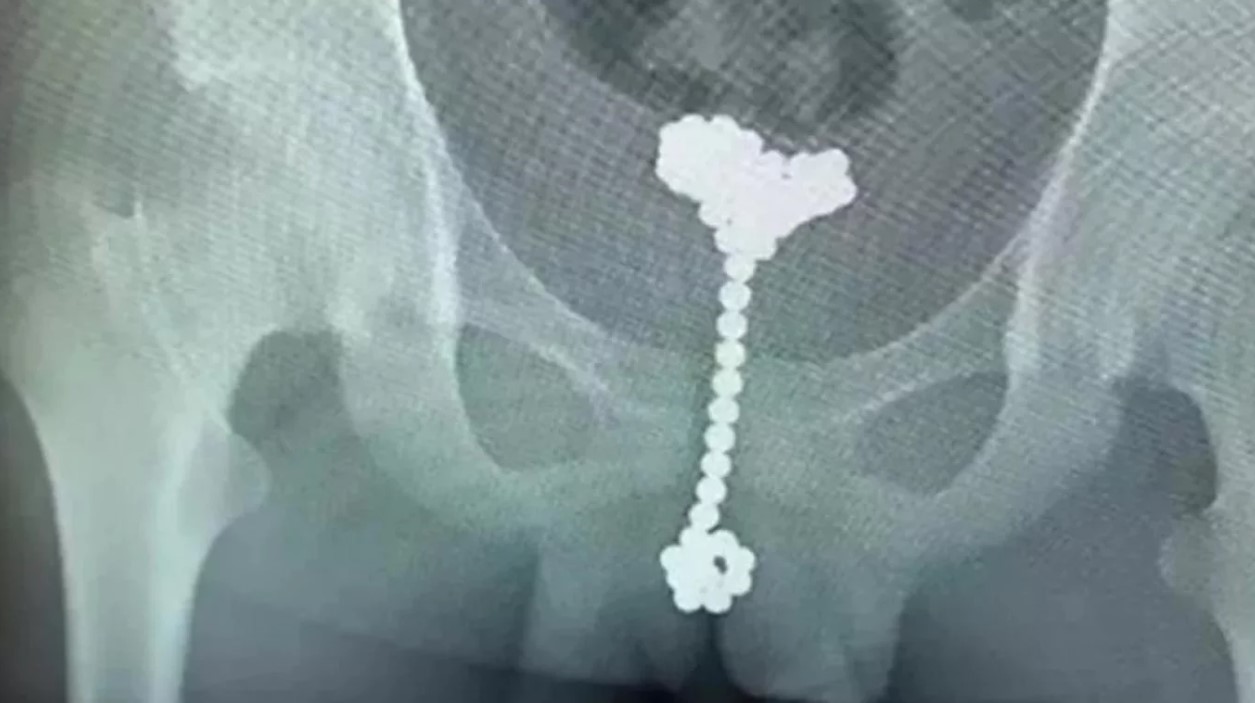

Un chico de 12 años pasó más de dos meses con 31 bolitas magnéticas en su pene y su vejiga. Por un fuerte dolor abdominal, el pequeño fue trasladado a un hospital en la ciudad de Wuhan, en el centro de China, donde la radiografía reveló que tenía dentro suyo una multiplicidad de "cuerpos extraños".

Luego de que le hicieran los estudios, el menor admitió a los médicos que se había introducido por el orificio del pene las 31 bolitas imantadas hacía unos 70 días.